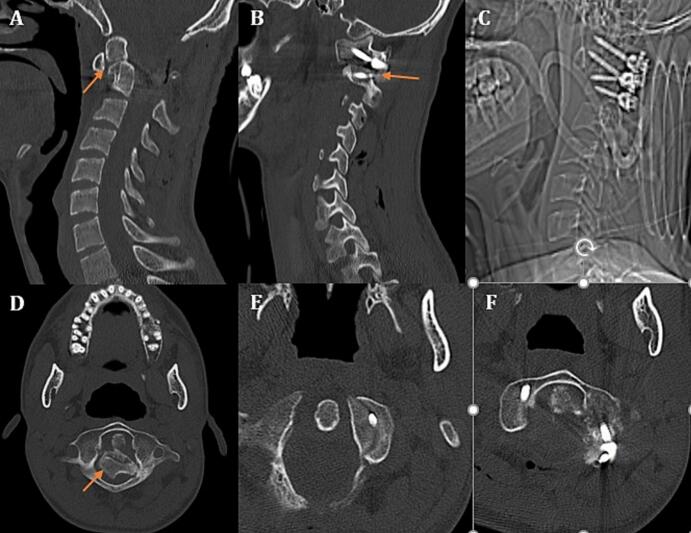

A 30-year-old man was referred to out center with quadriparesis and signs of myelopathy. He was in a car accident 6 months before the presentation, and has been admitted in a hospital due to head, face and neck trauma. He has been diagnosed with stable, type-II OF (Fig. 1A) and was discharged with a Philadelphia collar and instructions for close follow-up. He has undergone facial and mandibular internal fixation 2 weeks after the trauma. He was operated by maxillofacial surgeons during the same admission. In his post-operative course, he developed quadriparesia and distal paresthesia for what he had undergone vascular investigations with conventional and CT-angiogram (Fig. 1B) of carotid and vertebral arteries (Fig. 1C). Displaced OF and dislocated AAJ was missed in imaging investigations (Fig. 1B). The patient was discharged and did not refer for months afterward, till he presented to a neurosurgeon with progressing neurologic deficit. Initial evaluations revealed missed type-II OF with anterior AAD and bilateral locked C1-C2 facet joints (Fig. 1D).

Fig. 1.

A: Initial cervical sagittal CT-scan demonstrating a non-displaced type-II odontoid fracture (OF, arrow); B: displaced OF missed in sagittal brain CT-angiogram; C: normal brain CT-angiogram of the patient being performed after the maxillofacial surgery; D: delayed cervical sagittal CT-scan demonstrating displaced type-II OF with AAD showing posterior fibro-osseous bundle (arrow); E: cervical sagittal CT-scan demonstrating the C1-C2 locked facet (arrow); F: lateral cervical radiography demonstrating proximal, posteriorly displaced segment compressing upper cervical spinal cord segment and lower medulla.

In our spine surgery center, we further evaluated the patient with computed tomography (CT), magnetic resonance imaging (MRI), CT-angiography and dynamic cervical radiogram. Type-II OF with anterior displacement of distal segment associated with AAD and bilateral locked C1-C2 facet was identified (Fig. 1D, E). Posterior fibro-osseous bundle (bone callous) was connecting fracture segments (Fig. 1D). Proximal, posteriorly displaced segment, beside posterior fibro-osseous connecting bundle, was compressing upper cervical spinal cord segment and lower medulla (Fig. 1F).